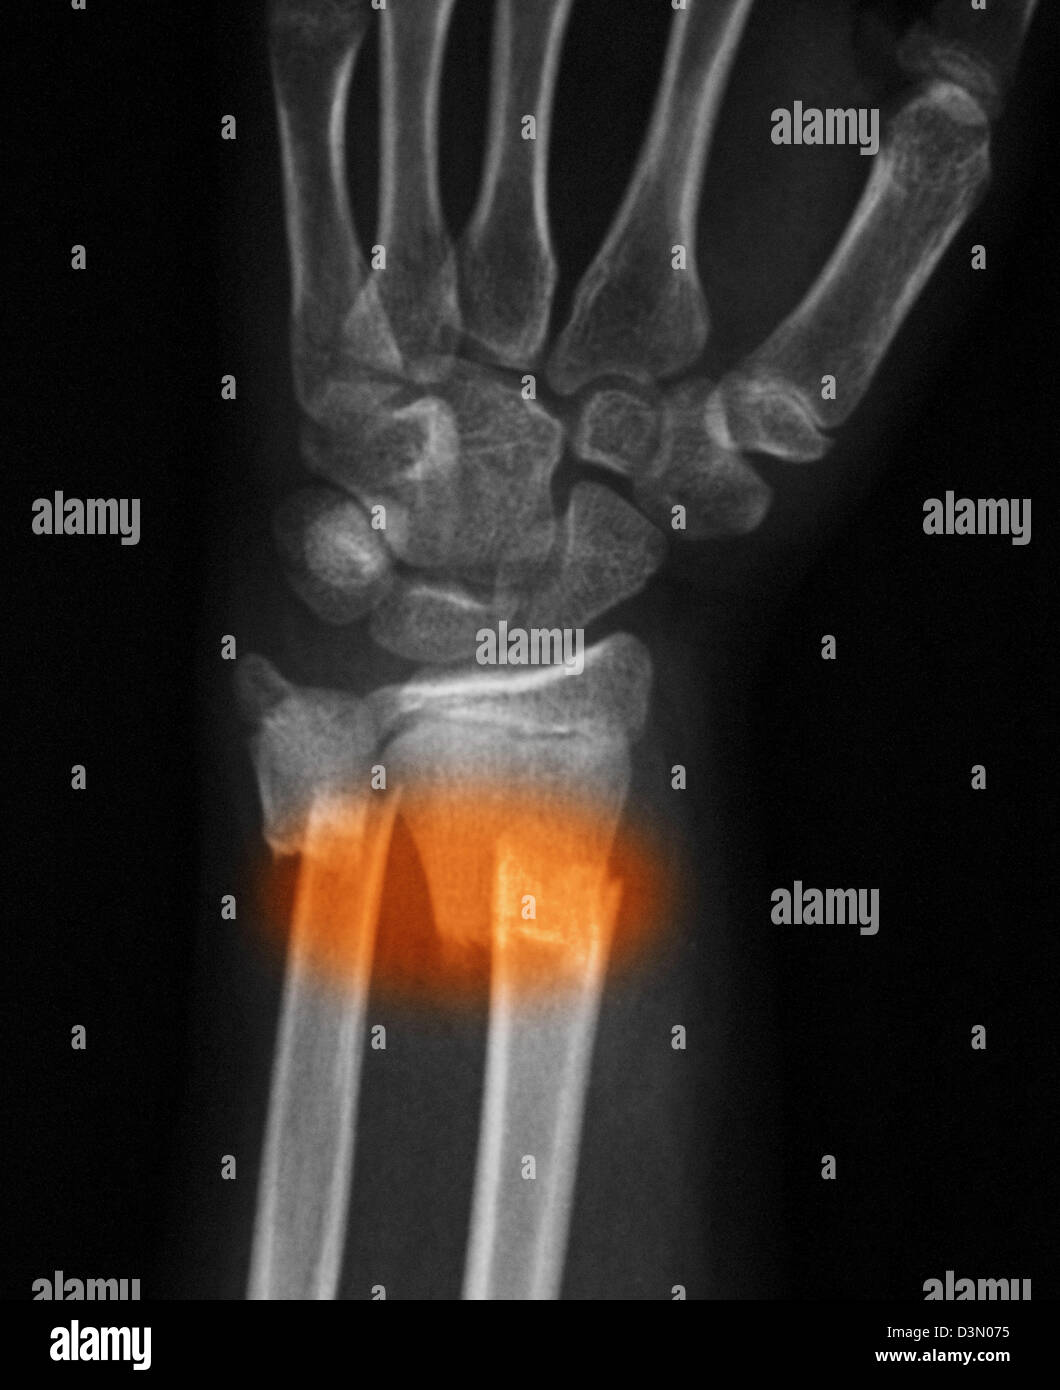

From www.alamy.com

Broken Wrist Fractured Radius and Ulna with Ulnar Shortening Stock Radius And Ulna Fracture Complications In Child The forearm is the part of the arm between the wrist and the elbow. An isolated ulna fracture may be. In most cases, the radius. Both bones in the forearm are affected. There are six types of forearm fractures in children: Distal radius fractures are the most common site of pediatric forearm fractures and generally occur as a result of. Radius And Ulna Fracture Complications In Child.